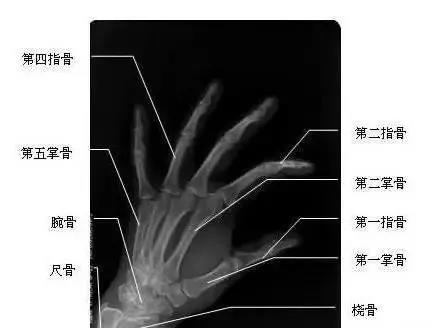

我們先來(lái)看一下雙手漂亮的“骨感”圖,這是雙手主要骨頭組成部分。骨頭外面覆蓋了肌肉、血管、神經(jīng)、筋膜、皮膚等組織。腱鞘,就是指纖維鞘+指滑膜鞘的雙層套管樣結(jié)構(gòu),對(duì)肌肉的肌腱起約束、支持和滑車(chē)等作用。所謂腱鞘炎,就是指肌腱及其周?chē)采w組織發(fā)生炎癥。腱鞘炎最常發(fā)生于手部或腕部,但也可發(fā)生于身體其他部位,如踝部。